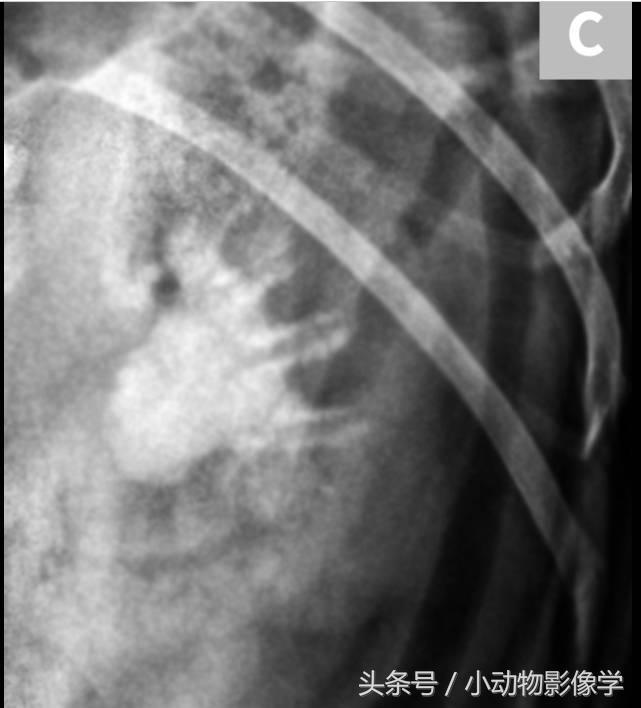

图7A、一只猫的腹部侧位平片,腹膜后隙的腹侧方向(箭头)有多个小型椭圆不透明矿物阴影叠加。这些线性排列的不透明矿物质从肾的尾部延伸到膀胱。

图7B、图7A中猫的超声图像,可见X光片上的结石(箭头)都分布于左输尿管内(三角箭头之间)。

图7C、同一只猫的顺行性超声引导肾盂造影影像,可见中度肾积水(H)和输尿管内多处充盈缺损(结石)(箭头)。尽管输尿管结石数量很多,但动物输尿管仍只是部分梗阻,因为阳性造影剂在结石远端(三角箭头)。